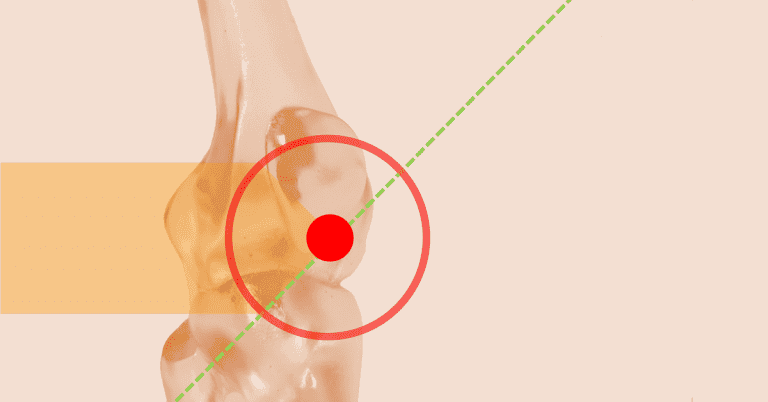

Figure 3. Enthesis. The circled area shows the junction between the tendon and bone, referred to as the “enthesis.”

The Enthesis

The enthesis is the region where a tendon, ligament, joint capsule, or muscle fascia attaches to the bone. It is a transitional tissue that serves as an anchor for soft tissues and transfers stress from these areas to the adjacent bone. (fig 3)

Enthesopathy is a term that indicates the presence of pathology in the enthesis, regardless of its etiology. (fig 4)